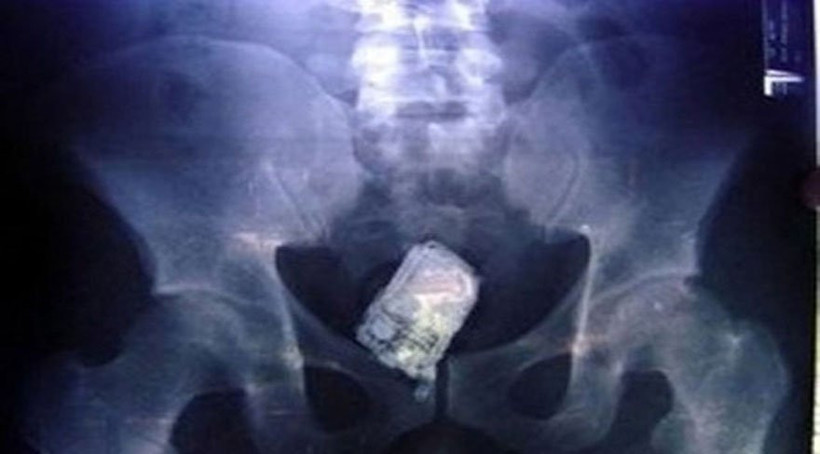

İnsanlar farklı sağlık sorunları nedeniyle acil servise başvuruyor, ancak bazı durumlar var ki hem hasta tarafından hem de doktor tarafından kelimelerle tarif edilemiyor. Daha önce dünyada örneklerini rastlandı ama bu kadarına değil. Birazdan okuyacağınız bu haber akıllara durgunluk veriyor. ÇALIŞAN BİR CEP TELEFONU; Amerika’da yaşanan olayda iddiaya göre bir avukat cep telefonuyla duş alıyordu, kayıp düştü ve cep telefonu anüsünden içeri girdi. Cep telefonunun çıkarılması için yapılan operasyon sırasında cep telefonu arada çalmayı sürdürüyordu.